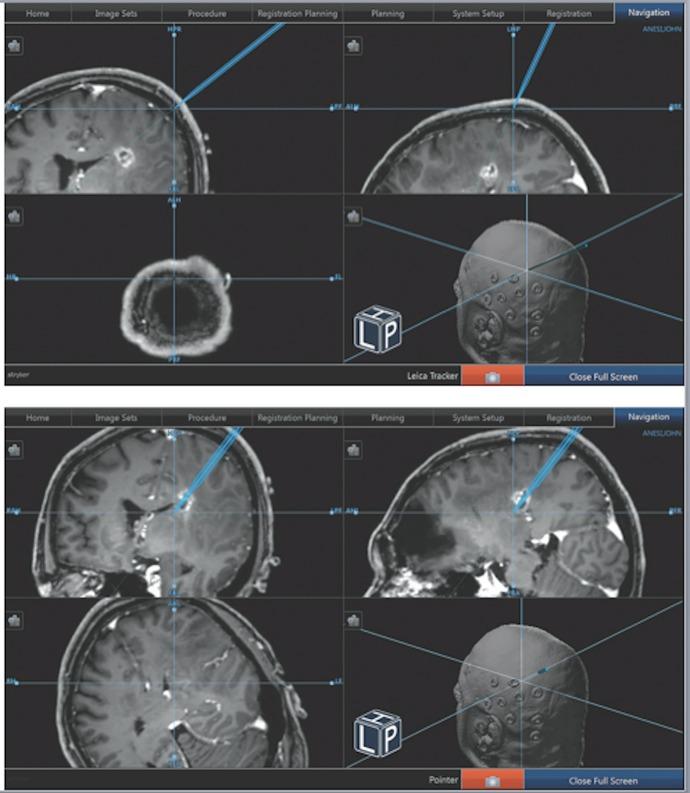

The surgical management of deep brain tumors is often challenging due to the limitations of stereotactic needle biopsies and the morbidity associated with transcortical approaches. We present a novel microscopic navigational technique utilizing the Viewsite Brain Access System (VBAS) (Vycor Medical, Boca Raton, FL, USA) for resection of a deep parietal periventricular high-grade glioma as well as another glioma and a cavernoma with no related morbidity. The approach utilized a navigational tracker mounted on a microscope, which was set to the desired trajectory and depth. It allowed gentle continuous insertion of the VBAS directly to a deep lesion under continuous microscopic visualization, increasing safety by obviating the need to look up from the microscope and thus avoiding loss of trajectory. This technique has broad value for the resection of a variety of deep brain lesions.

由于立体定向针吸活检的局限性以及经皮质入路相关的发病率,深部脑肿瘤的外科治疗通常具有挑战性。我们展示了一种新颖的显微导航技术,该技术利用Viewsite脑通路系统(VBAS)(Vycor Medical,美国佛罗里达州博卡拉顿)切除深部顶叶脑室周围高级别胶质瘤以及另一例胶质瘤和一例海绵状血管瘤,且无相关发病率。该入路使用安装在显微镜上的导航追踪器,将其设置到所需的轨迹和深度。它允许在连续显微镜观察下将VBAS轻柔地连续插入深部病变,通过避免从显微镜上抬头从而避免轨迹丢失来提高安全性。该技术对于切除各种深部脑病变具有广泛的价值。